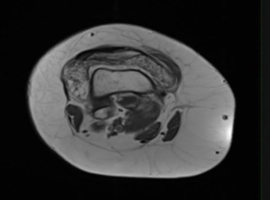

Citation: Rao M, Mohamed Haflah NHB, Bin Sani MH. Bilateral Knee Lipoma Arborescens. Case Rep Orthop Surg J. 2024; 3(3): 135.